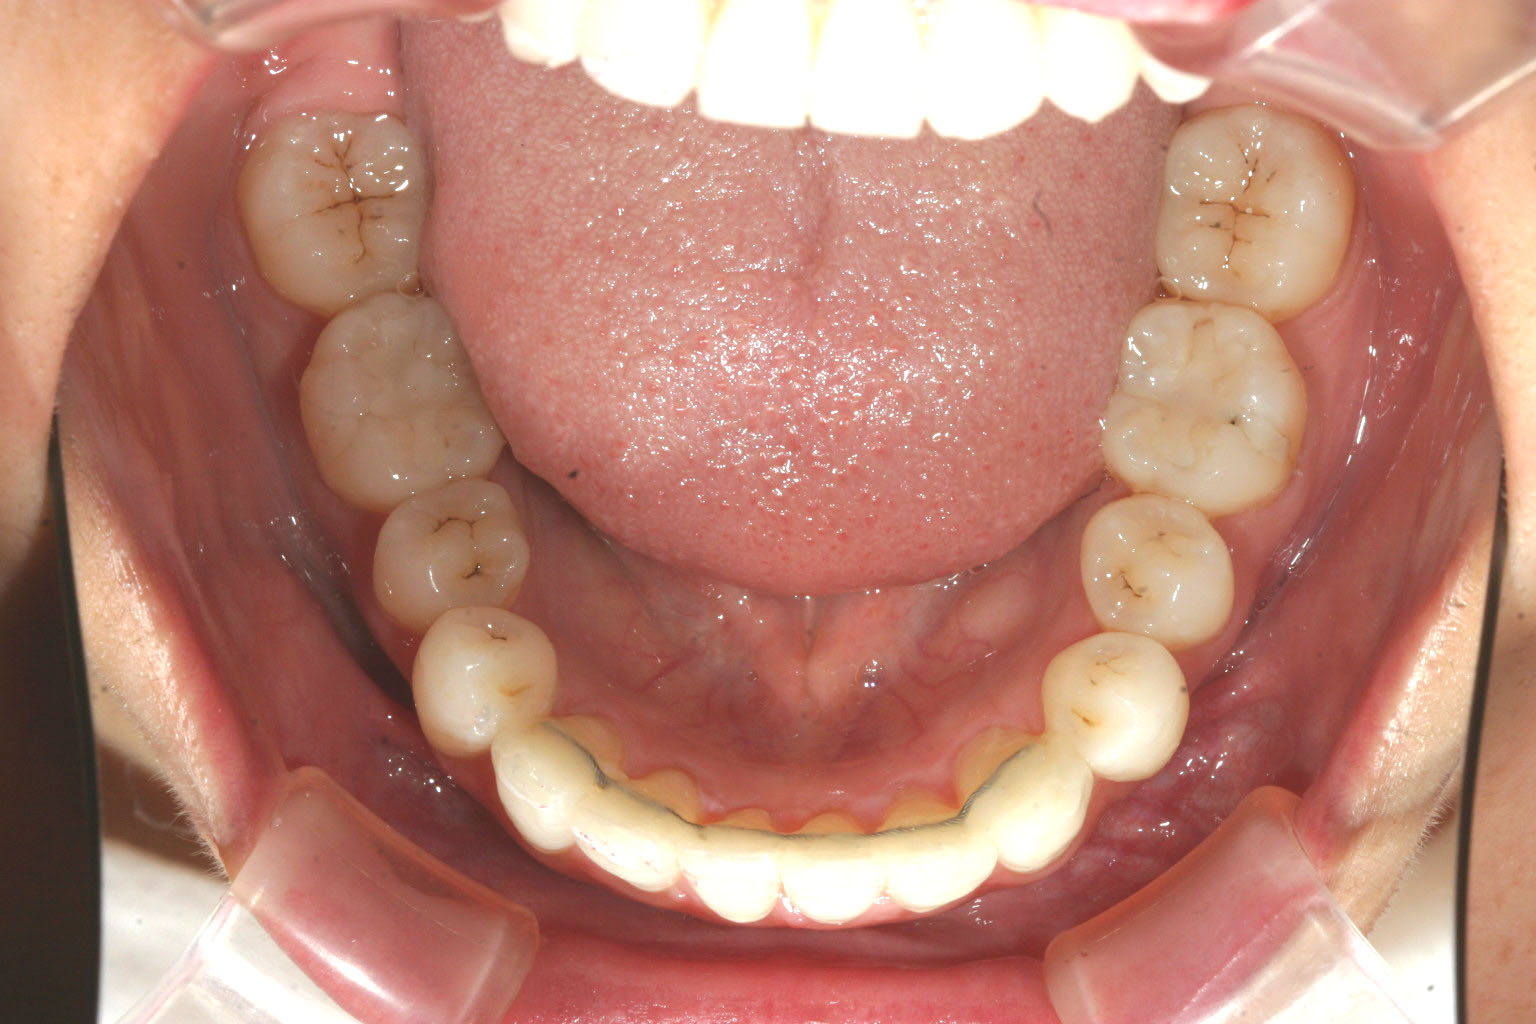

下顎小臼歯部が少しガタついてます。

小臼歯部も綺麗に改善してます。

こちらのケースは抜歯を右側上顎第一小臼歯だけと極力最小限にとどめて上下顎のオーバージェットを改善しました。

又臼歯部のかみ合わせが低い為自家製バイトアップジグにて臼歯部を挺出させて咬合を上げました。

これだけ上下顎前突が内に入れば口元のゴボっとした出具合も綺麗に改善されます。